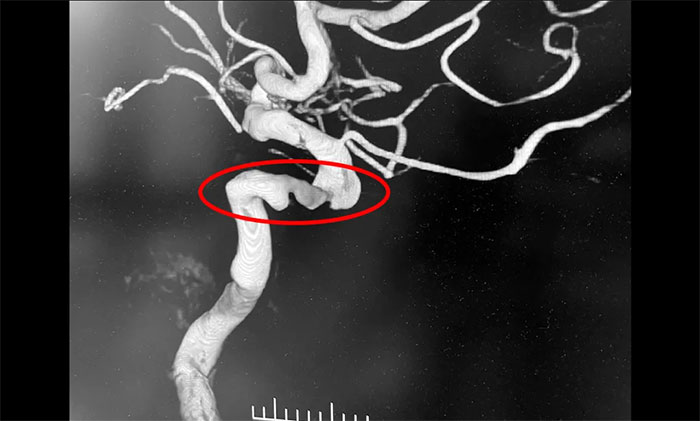

入院后,腦血管造影檢查確診:左頸內動脈海綿竇段、床突段多發(fā)動脈瘤,同時左頸內動脈起始段重度狹窄,眼動脈段狹窄,左大腦中動脈M1段閉塞。席剛明教授指出,從治療的原則上這兩種疾病是相互排斥的,血管狹窄的治療需要進行單抗甚至雙抗的一級卒中預防,也就是抗血小板治療;而動脈瘤的治療不能進行抗血小板治療,因為一旦動脈瘤破裂,之前的抗血小板治療會起到相反的作用,造成出血增加,所以治療便成了一個“復雜”而又“棘手”的問題。

患者病情表現(xiàn)為缺血性腦血管病,由于同時存在多支腦血管狹窄,而隨著年齡的增加,動脈粥樣硬化導致的血管狹窄也必然逐漸加重,因此抗血小板治療勢在必行,同時頸內動脈已經(jīng)出現(xiàn)了重度狹窄近閉塞,因此必須“架橋”,讓血流重新供應大腦半球;但是復雜的是,左頸內動脈海綿竇段、床突段多發(fā)動脈瘤瘤體角度刁鉆,形態(tài)不規(guī)則,隨時都有可能破裂出血,危及患者的生命安全,這個雷也必須得“拆”。神經(jīng)內科4A病區(qū)主任席剛明教授、神經(jīng)內科4A病區(qū)副主任王貴平博士會診后決定,通過一次介入手術,解決腦血管狹窄的同時處理動脈瘤,將“復雜”的病情“簡單”化,一次性解決兩個問題,同時避免分期手術帶來的一系列創(chuàng)傷。

▲ 頸動脈狹窄合并左頸內動脈海綿竇段、床突段多發(fā)動脈瘤